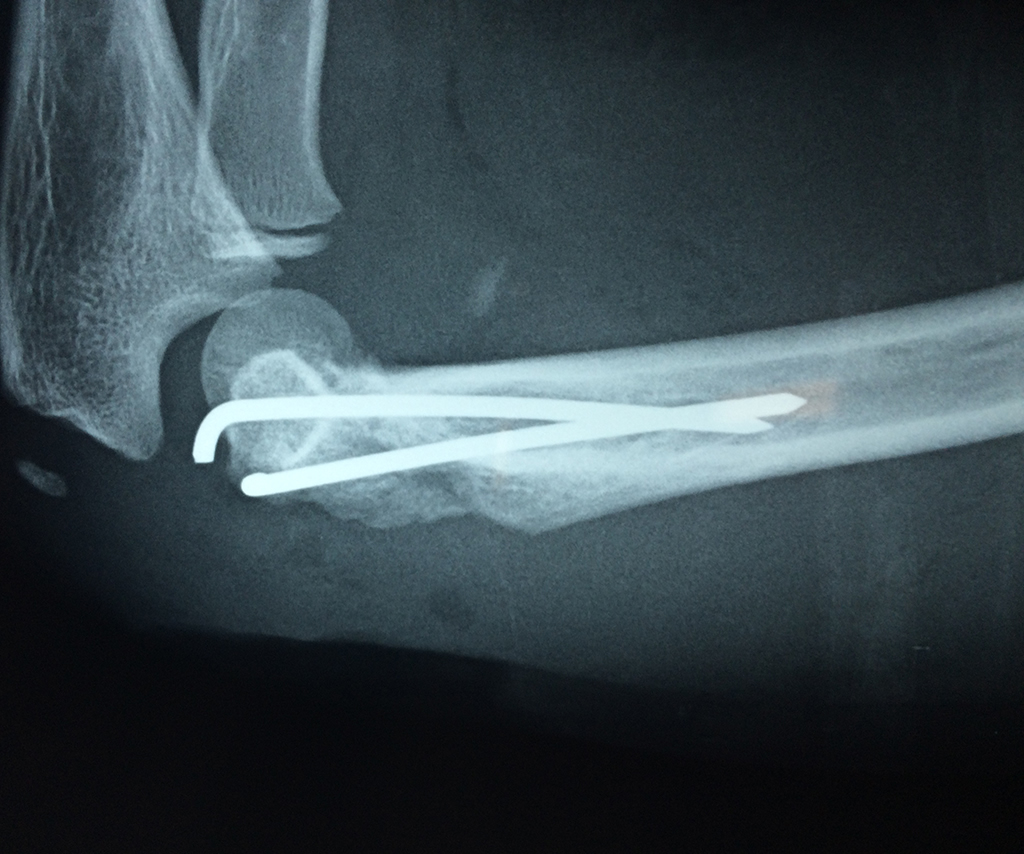

Cirugias en El Salvador - Codo

En anatomía humana, la articulación del codo es la que une el brazo con el antebrazo, conectando la parte distal del hueso húmero con los extremos proximales de los huesos cúbito y radio.

La articulación principal que constituye el codo se denomina humero radio-cubital y puede dividirse en dos partes bien diferenciadas, la articulación humero-radial y la humero-cubital.

Por otra parte el cúbito y el radio forman también una articulación entre si en las proximidades del codo, la cual se denomina articulación radio-cubital proximal.